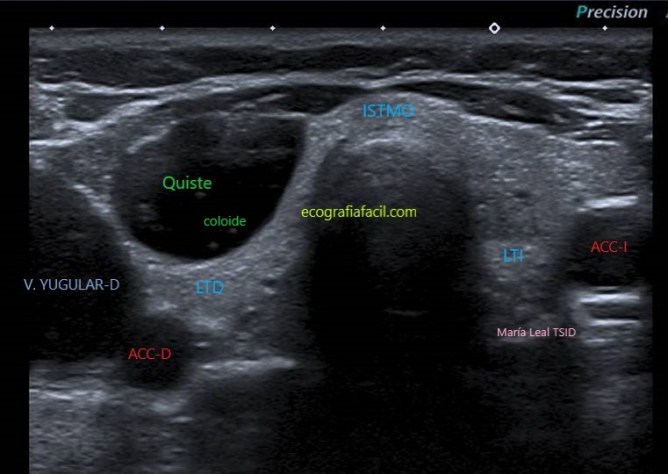

QUISTE:

Quiste

Los artefactos en “cola de cometa” son focos ecogénicos con forma en “V”. Se asocian con contenido coloide y son muy indicativos de benignidad cuando se encuentran dentro de componentes quísticos en los nódulos tiroideos.